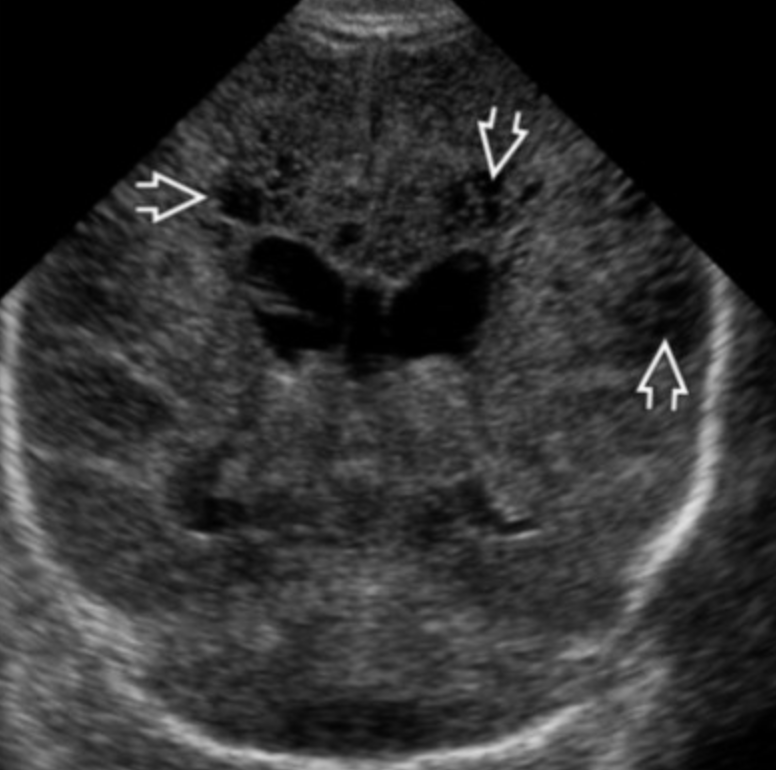

Germinal Matrix Hemorrhage

• The choroid plexus should not extend past the caudothalamic groove

• If you see bright stuff near there then suspect it is blood

• There is normally some increased echogenicity in the periventricular white matter

• So how do we know what is blood vs normal brain

• If prominently asymmetric = likely blood

• If area of increased echogenicity is as echogenic or more echogenic as the choroid plexus = likely blood

• Normal peri-ventricular brain should be echogenic but not more than the choroid plexus

• Can you identify borders of the echogenic area

• If yes = likely blood

• Normal brain will be more vague